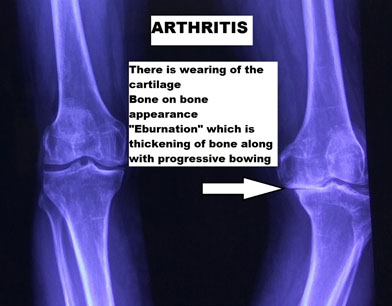

Arthritis is mostly wearing away of the smooth glistening cartilage which covers the ends of bone inside a joint and ensures smooth movement. When the cartilage is worn off, there are changes in the bone, which mainly hardens the bone (known as eburnation) and when bone rubs against bone leads to symptoms of arthritis.

Radiological findings in OA

X rays are taken to demonstrate arthritic changes. In weight-bearing joints like the knees, it is useful to take X-rays in the standing position to determine the extent of the damage. Mostly 2-3 views are recommended to understand the real extent of cartilage damage.

The knee joint has three compartments. As shown in the image, the inner side is medial, the outer is lateral, and the joint space between the knee cap (patella) and the thigh bone (femur) is the patella-femoral compartment. With advanced degeneration of the knee joint, there is a complete loss of joint space and new bone formation, which is called as “Osteophytes.”

An interesting aspect of arthritic knee pain is, even though the cartilage itself is the primary structure that suffers the damage, the pain in OA is due to secondary changes that happen in the bone and surrounding structure. There is swelling (Bone edema) and thickening (eburnation), which develops in OA, which stimulates the pain-sensing nerves in the bone. The joints also have a sensitive lining called synovium, whose thickening and inflammation can also lead to knee joint pain.